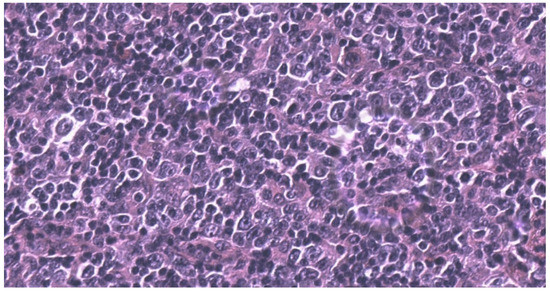

2. Case Report